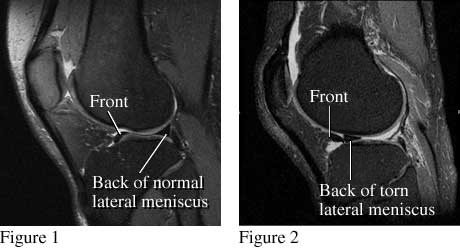

Figure 1 is a side view of the knee that shows the normal location of the outside, or lateral, meniscus. Figure 2 is a similar view that shows a piece of meniscus that has been torn and moved.